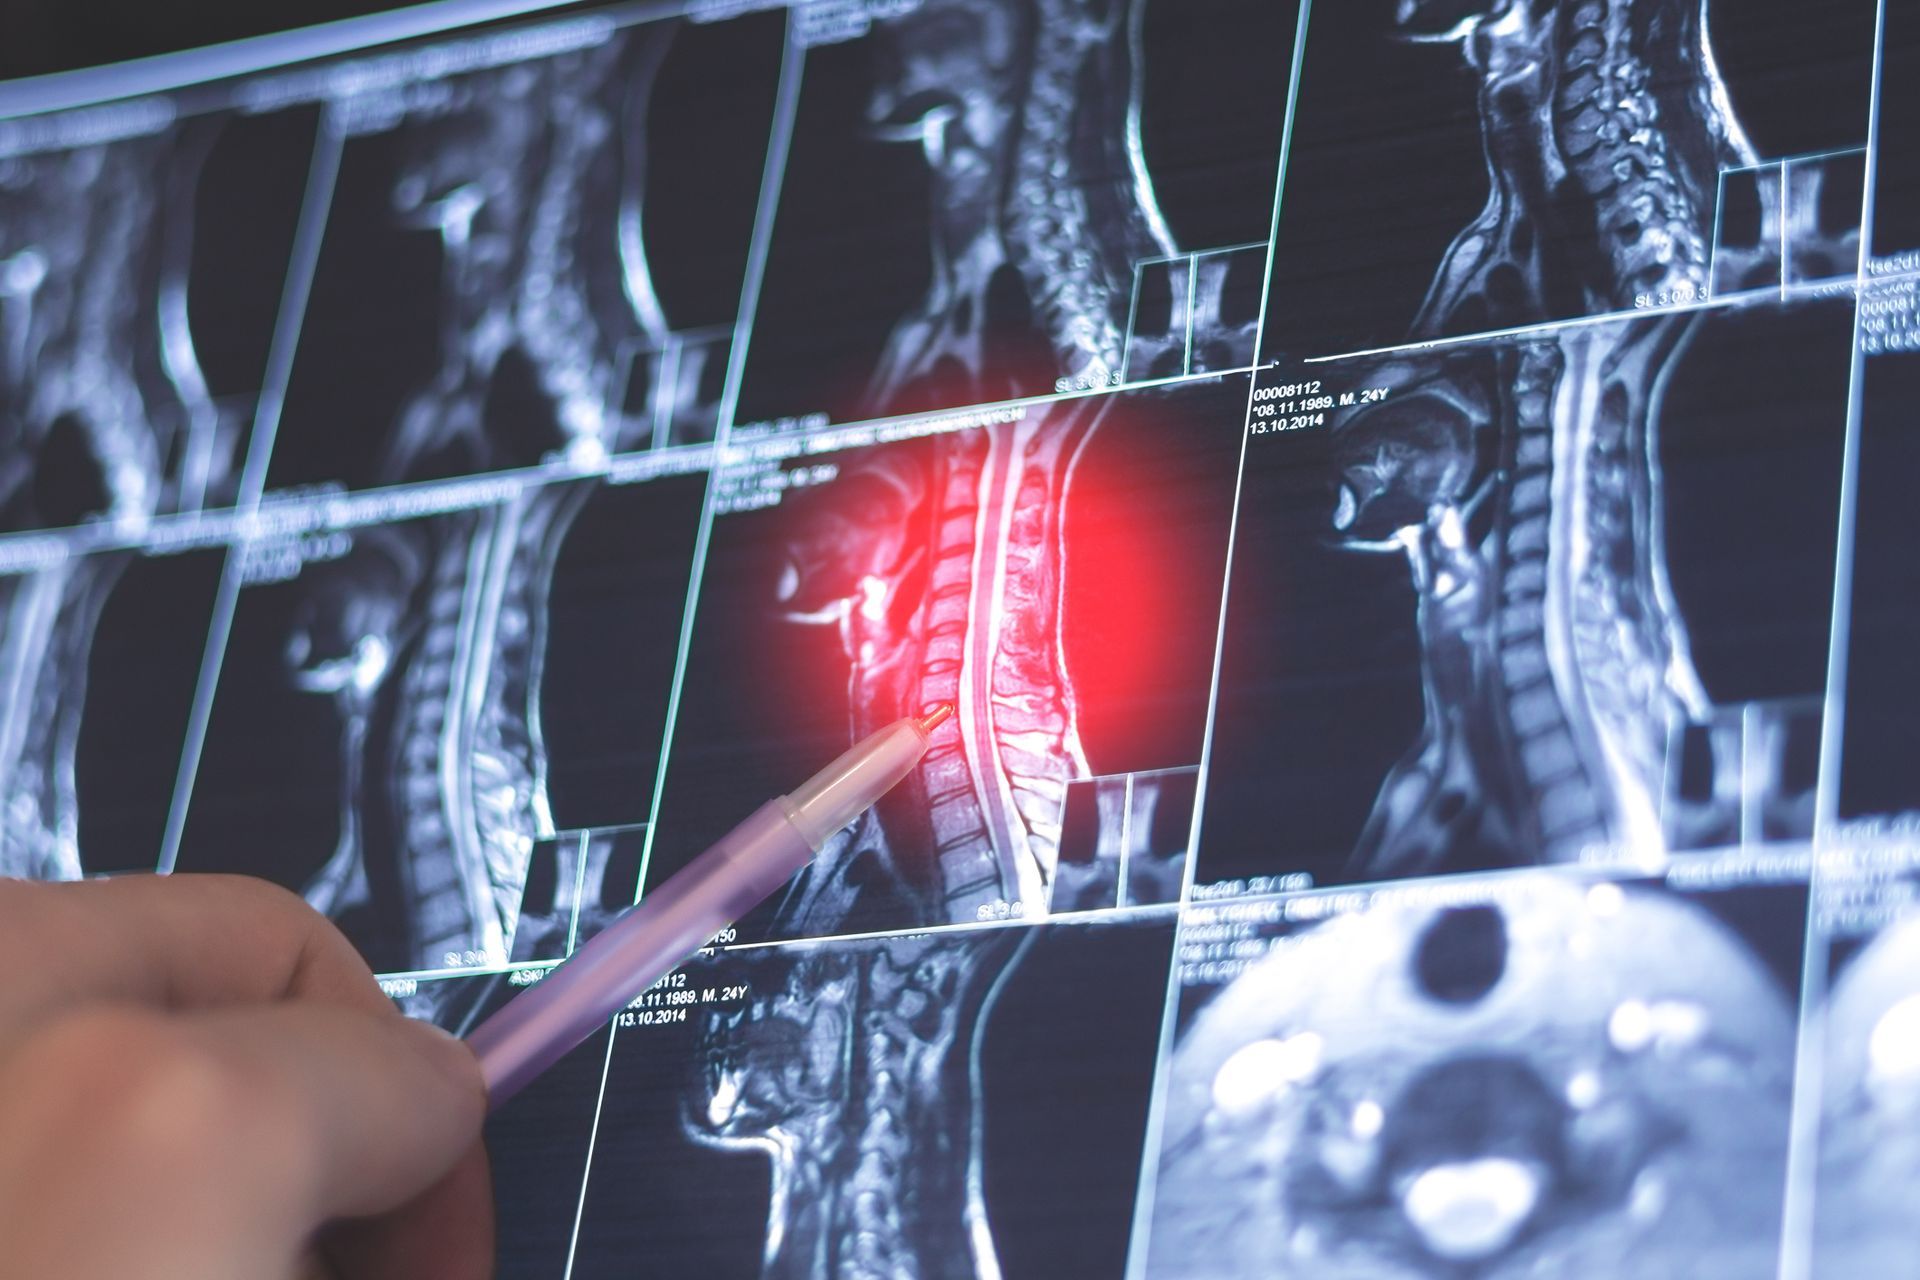

Uno dei principali ambiti di intervento del Dott. Michele Caniglia Neurochirurgo è la chirurgia vertebrale, con il trattamento di ernie cervicali e lombari, stenosi del canale vertebrale e neoplasie del rachide.

L’approccio clinico è sempre personalizzato, con attenzione a preservare la funzionalità e ridurre il dolore post-operatorio. L’esperienza maturata in numerosi casi clinici consente di offrire soluzioni mirate, in stretta collaborazione con altri specialisti, per garantire una presa in carico globale del paziente.

Ernia del disco cervicale e lombare

Patologia degenerativa della colonna vertebrale che causa dolore, formicolii e deficit motori. La chirurgia consente di liberare le radici nervose compresse, migliorando la qualità di vita.

Stenosi lombare e cervicale

Restringimento del canale vertebrale che provoca dolore e difficoltà motorie. L’intervento mira a decomprimere le strutture nervose e ripristinare la funzionalità.